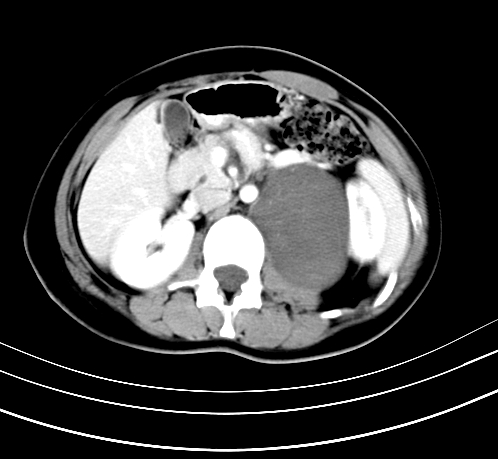

延时10分钟

重建

神经纤维瘤病

支持神经纤维瘤。

支持 神经纤维瘤病。